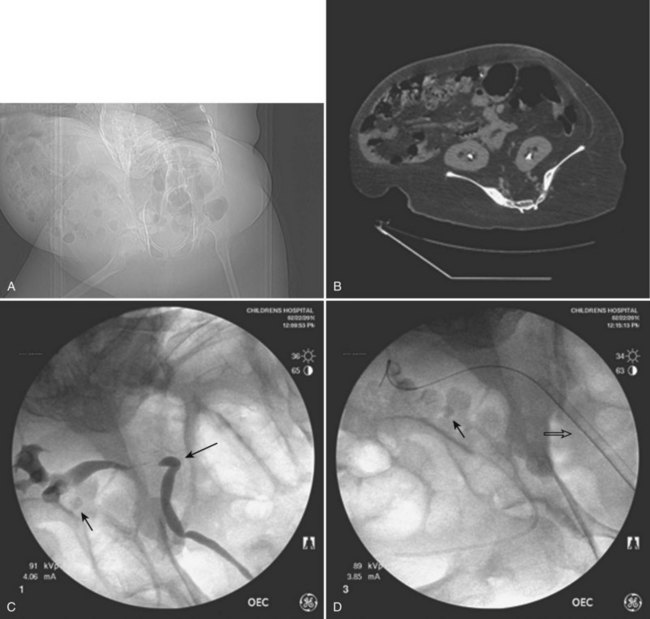

Much planning is required prior to embarking on PCNL in children. Films must first be reviewed scrupulously to determine if the stone(s) is/are amenable to a percutaneous procedure. Nephrocalcinosis in children, for example, may be confused with staghorn calculi; the etiology and treatment are very different (Fig. 135–8). Infection is the most common causative agent in the formation of a staghorn calculus, and PCNL is a first-line therapy. The most frequent causes of nephrocalcinosis are hereditary tubulopathies and vitamin D intoxication (Ammenti et al, 2009). Medullary sponge kidney is a renal malformation characterized by cystic anomalies of precalyceal ducts, which is frequently associated with nephrocalcinosis and stone formation (Gambaro et al, 2006). Nephrocalcinosis is most often not amenable to successful endourologic treatment(s) because calculi are intraparenchymal and thus outside the collecting system. Management is often medical and aimed at prevention of further nephrocalculi, a cause of worsening renal function.

Figure 135–8 A 9-year-old boy with cerebral palsy and gross hematuria. CT scan demonstrated bilateral nephrolithiasis (A) thought to be staghorn calculi. Plain radiograph (B) and bilateral retrograde pyelograms (C and D) correlate to show nephrocalcinosis (white circles and white arrows, respectively) reflective of medullary sponge kidney disease. Subsequent metabolic workup revealed renal tubular acidosis (RTA) with hypercalciuria.